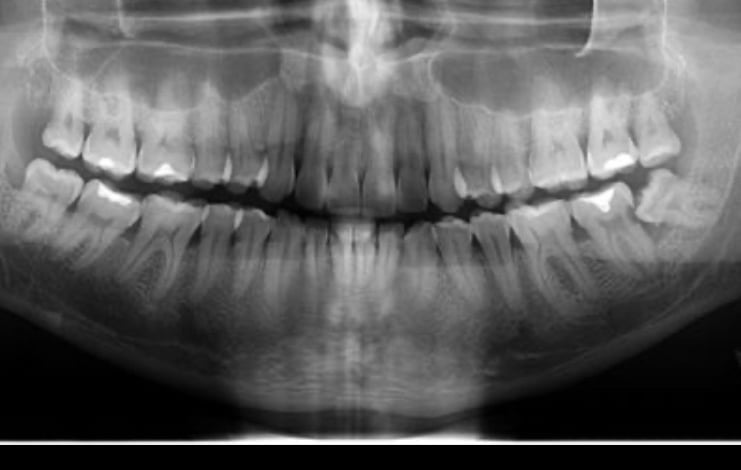

Exame de imagem

Na odontologia, tanto exames de imagem quanto exames laboratoriais, tem papel fundamental para um diagnostico preciso, planejamento adequado e segurança do paciente. Exames de imagem ajudam a ver o que esta escondido e planejar corretamente. Exames laboratoriais trazem segurança, avaliando o paciente como um todo.